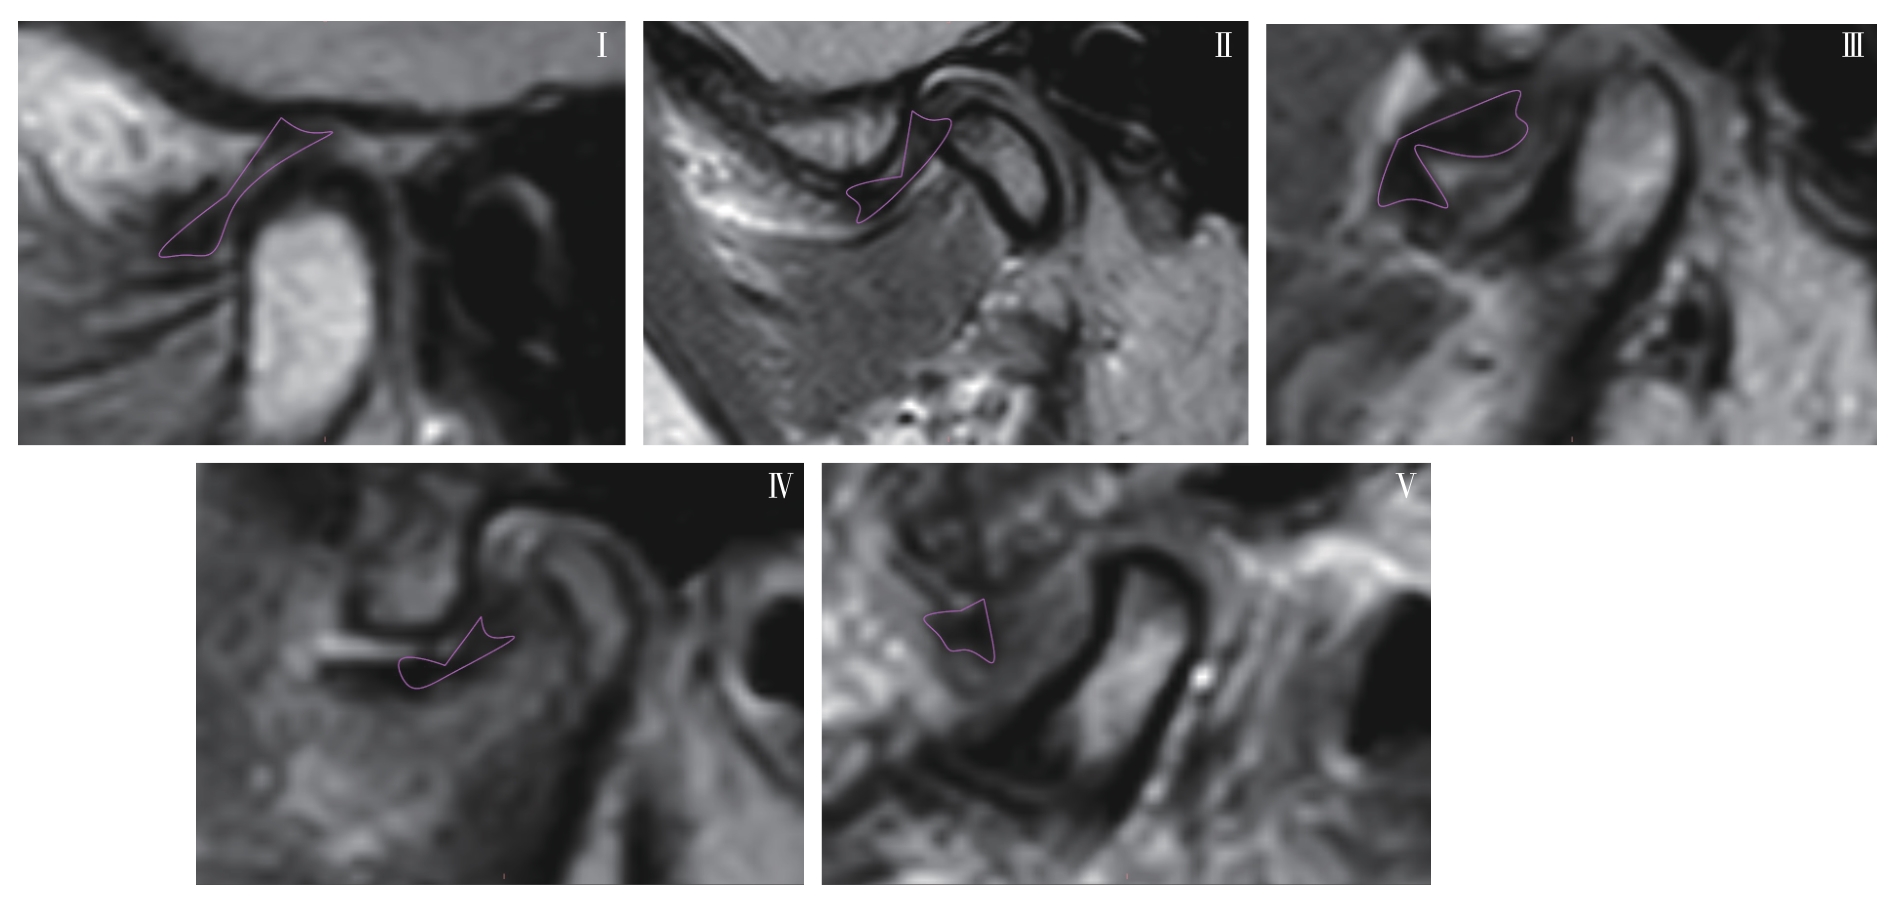

| 图6 关节盘变形程度分型 Note: Oblique sagittal PDWI images. Typical articular disc morphology of type Ⅰ‒Ⅴ. |

| Fig 6 Classification of articular disc deformation degrees |